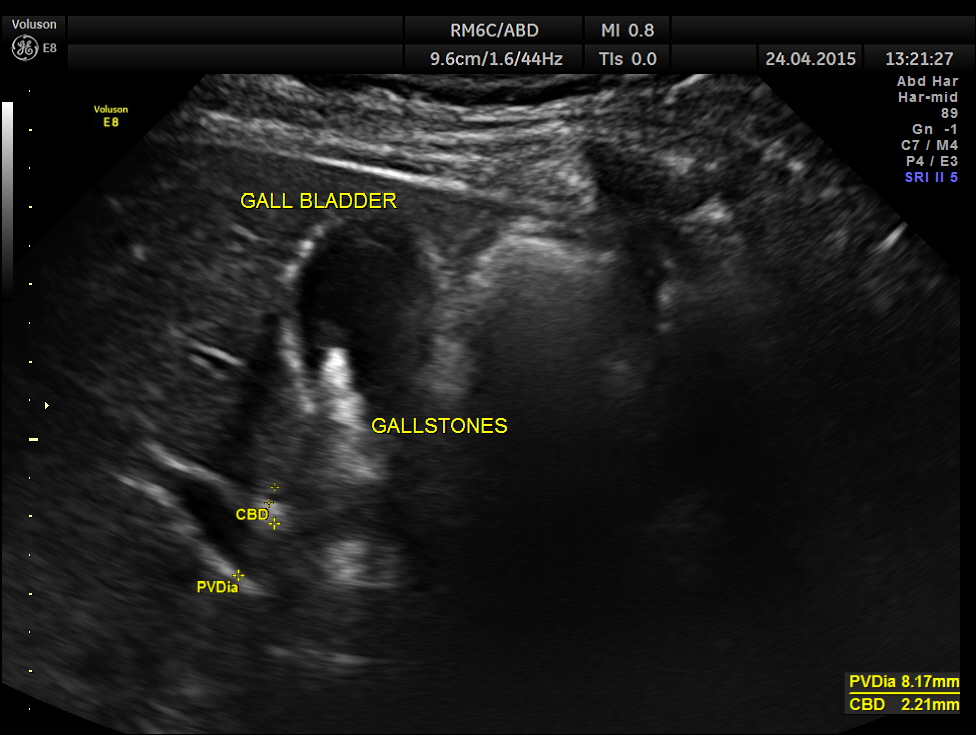

He had undergone an ultrasound examination 10 years ago for frequency and hesitancy and was found to have benign prostatic hypertrophy . He was started on oral alpha blockers and after 3 months he stopped that as he was symptomatically better. He also had gallstones at that time. At present he was on oral hypoglycaemic drugs and anti hypertensive. His random blood sugar was around 250 mgm/dl and his BP was 170/80 mms of Hg.

His ultrasound at present showed :

Gallstones were seen.